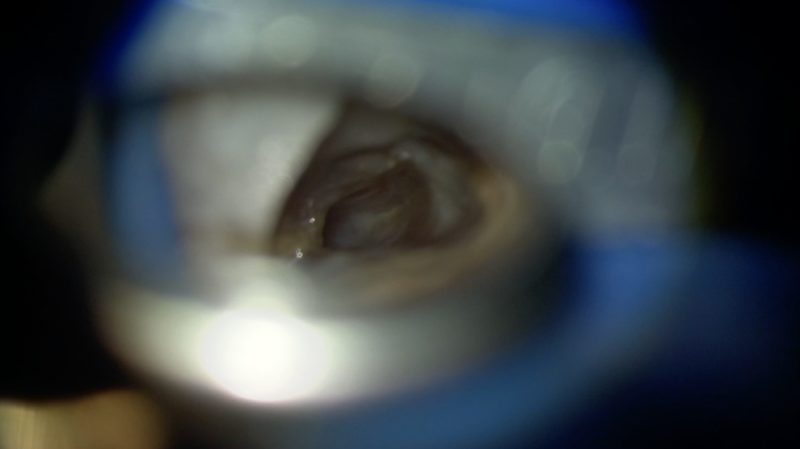

根管の形態はVertucci TypeⅡいわゆるY字型で、根管内には根管充填剤やデブリがたくさん残っていました。

清掃が進んで根管内が明るく見やすくなってくるとクラックも見つかりました。